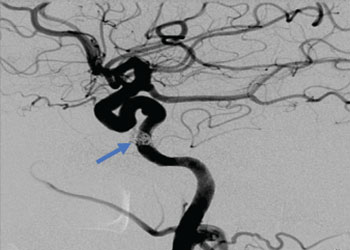

Endovascular:

CME:

Symptomatic Near-Occlusion of the Carotid Artery

Author: Jonathan L. Brisman M.D., F.A.C.S., Read More!

Right Vertebral Artery Compression Syndrome

Author: Artem Y. Vaynman M.D., F.A.A.N.S., F.A.C.S., Read More!

Direct Carotid Cavernous Fistula (CCF)